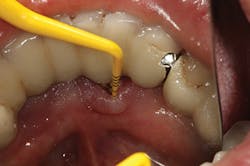

Late implant complications occur after the implant has integrated and the final prosthesis has been placed. Recognition of these complications via radiographic and clinical analysis is extremely important since many of these problems can be corrected if detected early. On the other hand, if allowed to progress, a minor complication can often result in loss of the implant and/or prosthesis. Late complications of the dental implant fall into the category of biologic or mechanical complications. Late biologic complications are those in which the peri-implant soft and hard tissues are affected. Peri-implant mucositis describes a reversible inflammatory reaction in the mucosa adjacent to an implant,(8) a term that has become known as implant gingivitis. Studies show that the prevalence of peri-implant mucositis can be as high as 50% to 80% of implants in function(9) with the etiology of peri-implant mucositis being bacterial plaque. Typical clinical presentation includes erythema, edema, swelling, and redness (Figs. 1 and 1a). Although bleeding upon probing and increased probing depths are not always indicative of peri-implant mucositis,(10) the absence of these two factors usually means implant health.(11)

Treatment of peri-implant mucositis can often be accomplished via nonsurgical mechanical therapy. Although systemic antibiotics have been shown to reduce inflammation associated with peri-implant gingival tissue, as a monotherapy, they have been shown to be ineffective due to the bacterial recolonization of the implant surface without mechanical debridement.(12) Studies show that proper scaling and root planing with attention to bacterial plaque removal can be effective in reducing peri-implant mucositis lesions.(13) Localized drug delivery has also shown to have a positive effect in reducing mucositis lesions in conjunction with mechanical debridement (Fig. 2), especially in the areas of the mouth that are hard to reach.(14) After nonsurgical intervention, the patient should be recalled within three weeks. If no resolution of the inflammation has occurred, surgical intervention should occur.(15)